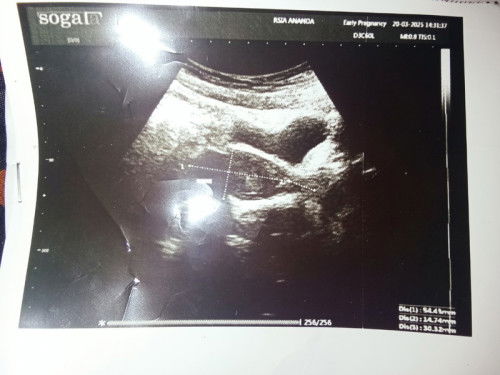

Assalamualaikum bunda bunda saya baru habis kuret Kamis kemarin Bun karena bnyk banget keluar darah segar sama perut kram dan pinggang sakit pas di USG kemaren udah tidak ada lagi kantung kehamilan dalam rahim udah banyak keluar tinggal tersisa dikit dirahim Bun, sedih Bun baru merasa senang karena hamil tapi Tuhan berkehendak lain. Sharing dong bunda bunda yg pernah merasakan kuret apakah bisa hamil lagi 😭#mohonbantujawabbunda #Sharingdong_Bund #sharing